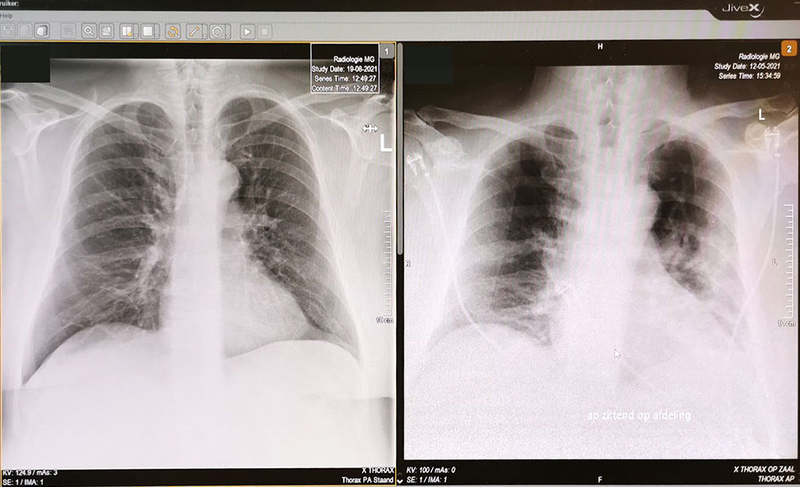

moje płuca po koronie

Zdjęcia moich płuc. Z prawej w dniu kiedy mnie przywieziono do szpitala, 12 maja 2021 a z prawej 3 miesiące po koronie,18 sierpnia 2021 r.